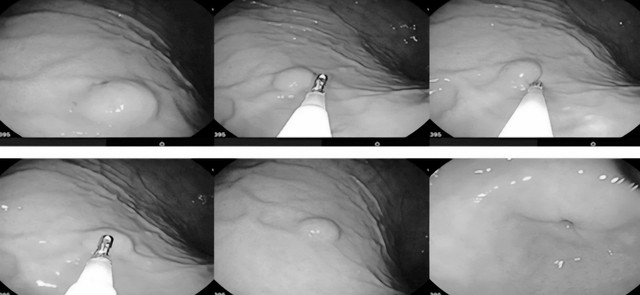

Hình ảnh khối u dưới biểu mô dạ dày, kích thước khoảng 1,5 mm, xuất phát từ lớp cơ của dạ dày. Ảnh: BVCC.

Bệnh nhân N.H.T. (61 tuổi, ở xã Vĩnh Tường, Nghệ An) vào viện trong tình trạng đau bụng, nôn. Các bác sĩ chỉ định chụp cắt lớp vi tính có tiêm thuốc và nội soi dạ dày. Qua nội soi, bác sĩ xác định đây là u dưới biểu mô dạ dày, kích thước khoảng 1,5 mm, xuất phát từ lớp cơ của dạ dày.